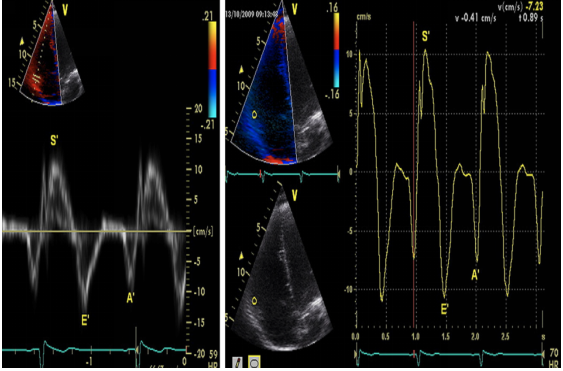

(3)组织多普勒(TDI)和TDI测量的三尖瓣环运动:我们一般选择脉冲波组织多普勒(TDI)在右室基底段游离壁来测量。其参考图像如图16所示。

图片

图16. RV-TDI的测量

典型的TDI包括三个波:顶点向上的收缩波(Sm)(S’),远离顶点的早期舒张波(Em)(E’)和晚期舒张波(Am)(A’),收缩波Sm前的等容收缩IVC。Sm(S’)的参考值常规大于11 cm/s,若小于10 cm/s,则代表收缩功能的明显下降。Sm和Em之间有等容舒张期,Am和Sm之间有等容收缩期。

(5)组织多普勒(LV-TDI):心尖四腔心切面,在二尖瓣瓣环处或侧壁处,取样容积5~10 mm进行测量。典型的LV-TDI图像如图25所示。

图25. LV-TDI的测量

收缩期的Sa(s’)峰,舒张早期Ea(e’)峰和舒张晚期Aa(a’)峰。Ea(e’)反映心肌的松弛能力,在侧壁测量的数值高于室间隔壁测量的值,其正常参考值为大于10 cm/s(侧壁)和8 cm/s(室间隔);一般来说,Aa(a’)大于8 cm/s。

②TDI下在心尖五腔心切面测量,取样容积放置于二尖瓣环,获得组织多普勒速度图图32。Sa(s’)波结束至Ea(e’)开始之前,为IVRT。Aa(a’)结束至Sa(s’)波开始之前为IVCT。Sa(s’)波持续时间为ET。

图32. TDI 测量LV MPI,Tei=(IVCT+IVRT)/ET

左室Tei 指数范围为0.39±0.10,值越大,代表心功能下降越明显。